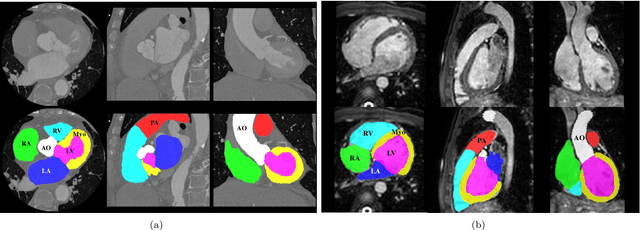

Abstract:Knowledge of whole heart anatomy is a prerequisite for many clinical applications. Whole heart segmentation (WHS), which delineates substructures of the heart, can be very valuable for modeling and analysis of the anatomy and functions of the heart. However, automating this segmentation can be arduous due to the large variation of the heart shape, and different image qualities of the clinical data. To achieve this goal, a set of training data is generally needed for constructing priors or for training. In addition, it is difficult to perform comparisons between different methods, largely due to differences in the datasets and evaluation metrics used. This manuscript presents the methodologies and evaluation results for the WHS algorithms selected from the submissions to the Multi-Modality Whole Heart Segmentation (MM-WHS) challenge, in conjunction with MICCAI 2017. The challenge provides 120 three-dimensional cardiac images covering the whole heart, including 60 CT and 60 MRI volumes, all acquired in clinical environments with manual delineation. Ten algorithms for CT data and eleven algorithms for MRI data, submitted from twelve groups, have been evaluated. The results show that many of the deep learning (DL) based methods achieved high accuracy, even though the number of training datasets was limited. A number of them also reported poor results in the blinded evaluation, probably due to overfitting in their training. The conventional algorithms, mainly based on multi-atlas segmentation, demonstrated robust and stable performance, even though the accuracy is not as good as the best DL method in CT segmentation. The challenge, including the provision of the annotated training data and the blinded evaluation for submitted algorithms on the test data, continues as an ongoing benchmarking resource via its homepage (\url{www.sdspeople.fudan.edu.cn/zhuangxiahai/0/mmwhs/}).

Abstract:Non-invasive detection of cardiovascular disorders from radiology scans requires quantitative image analysis of the heart and its substructures. There are well-established measurements that radiologists use for diseases assessment such as ejection fraction, volume of four chambers, and myocardium mass. These measurements are derived as outcomes of precise segmentation of the heart and its substructures. The aim of this paper is to provide such measurements through an accurate image segmentation algorithm that automatically delineates seven substructures of the heart from MRI and/or CT scans. Our proposed method is based on multi-planar deep convolutional neural networks (CNN) with an adaptive fusion strategy where we automatically utilize complementary information from different planes of the 3D scans for improved delineations. For CT and MRI, we have separately designed three CNNs (the same architectural configuration) for three planes, and have trained the networks from scratch for voxel-wise labeling for the following cardiac structures: myocardium of left ventricle (Myo), left atrium (LA), left ventricle (LV), right atrium (RA), right ventricle (RV), ascending aorta (Ao), and main pulmonary artery (PA). We have evaluated the proposed method with 4-fold-cross validation on the multi-modality whole heart segmentation challenge (MM-WHS 2017) dataset. The precision and dice index of 0.93 and 0.90, and 0.87 and 0.85 were achieved for CT and MR images, respectively. While a CT volume was segmented about 50 seconds, an MRI scan was segmented around 17 seconds with the GPUs/CUDA implementation.